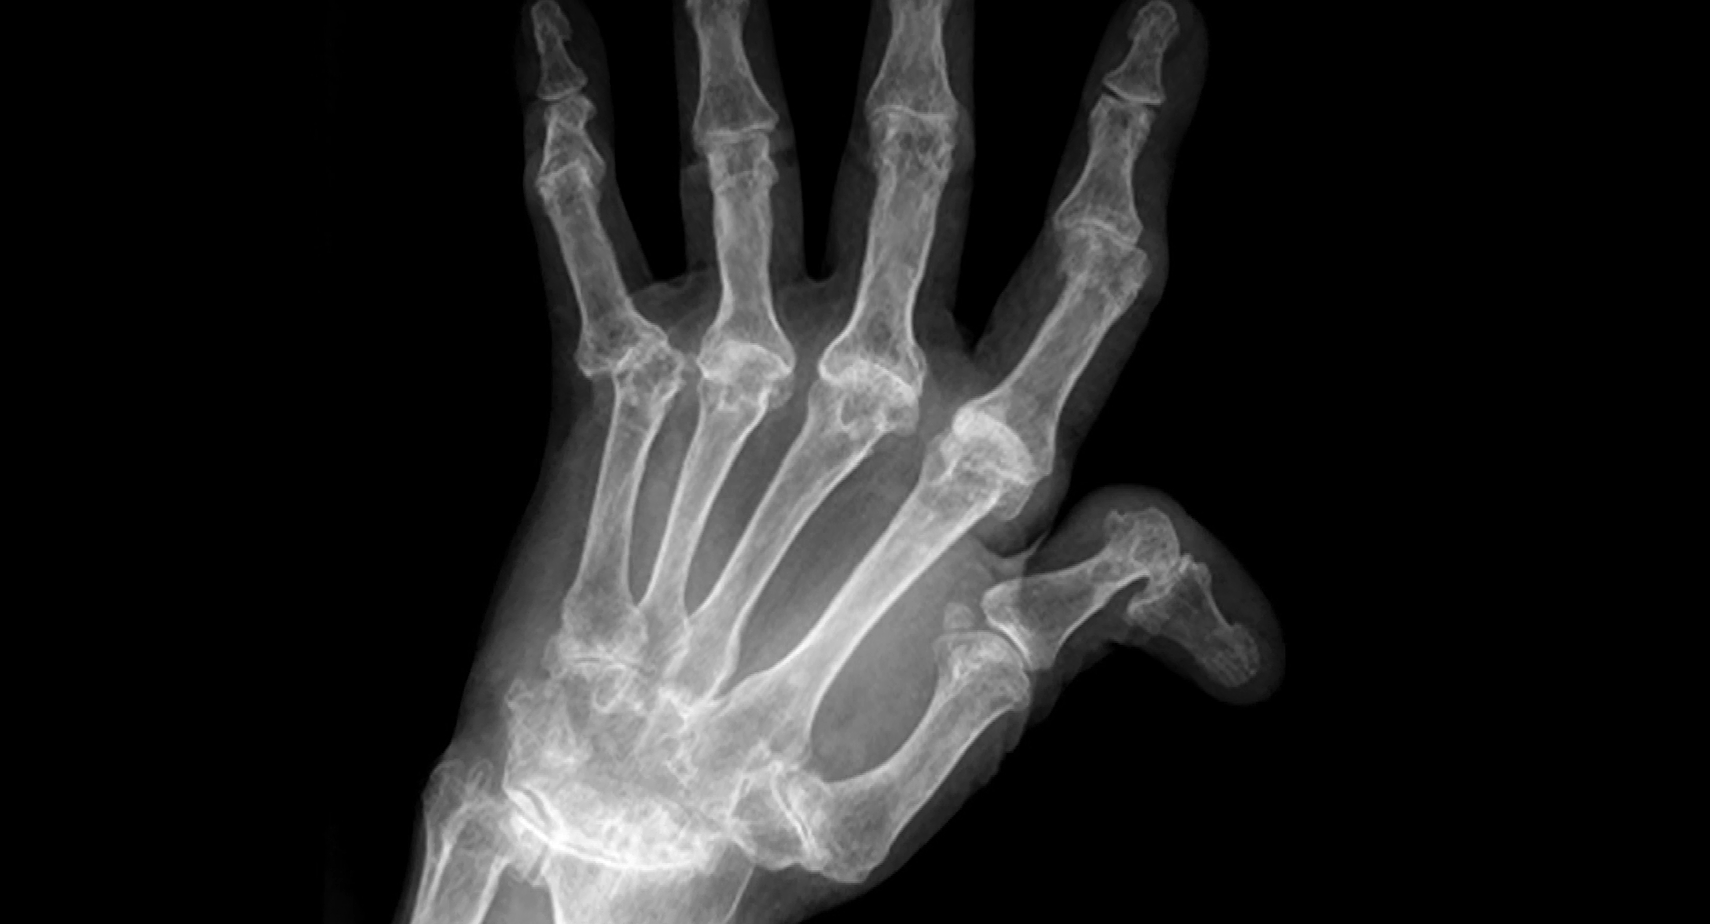

류마티스 관절염은 시간이 지나면서 연골과 뼈를 녹이고, 손가락이 휘고 발가락이 틀어져 걷기조차 어려워지는 심각한 병입니다. 더 무서운 점은, 이 염증이 심장과 폐, 혈관으로 번지면 심근경색, 뇌졸중, 폐섬유화와 같은 치명적인 합병증으로 이어질 수 있다는 사실입니다.

✅ 간단한 혈액검사와 엑스레이만으로도 조기 진단이 가능하니, 증상이 있다면 꼭 전문의를 찾아가세요.